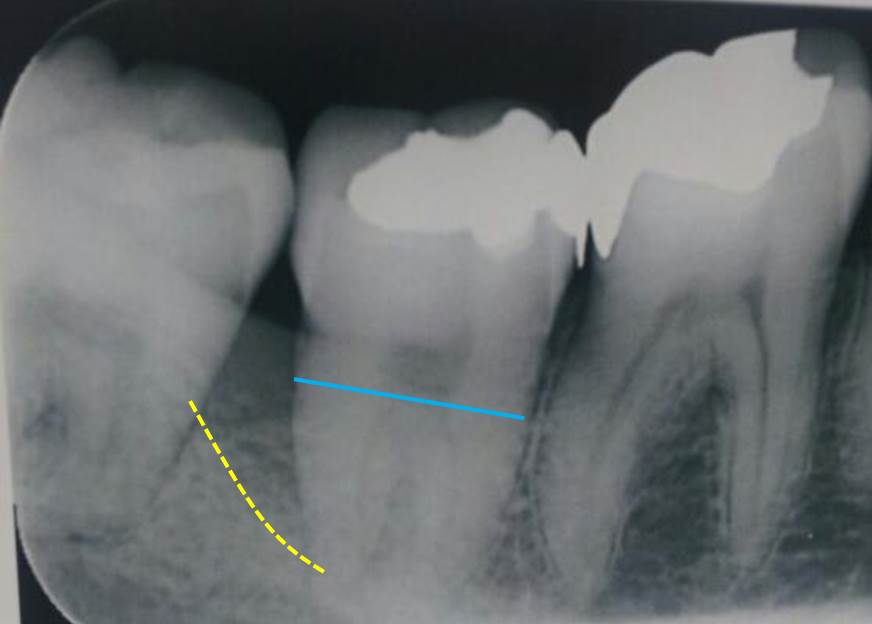

レントゲン写真です。黄色の点線が骨欠損底部(骨が吸収したライン)になります。重度の歯周炎です。